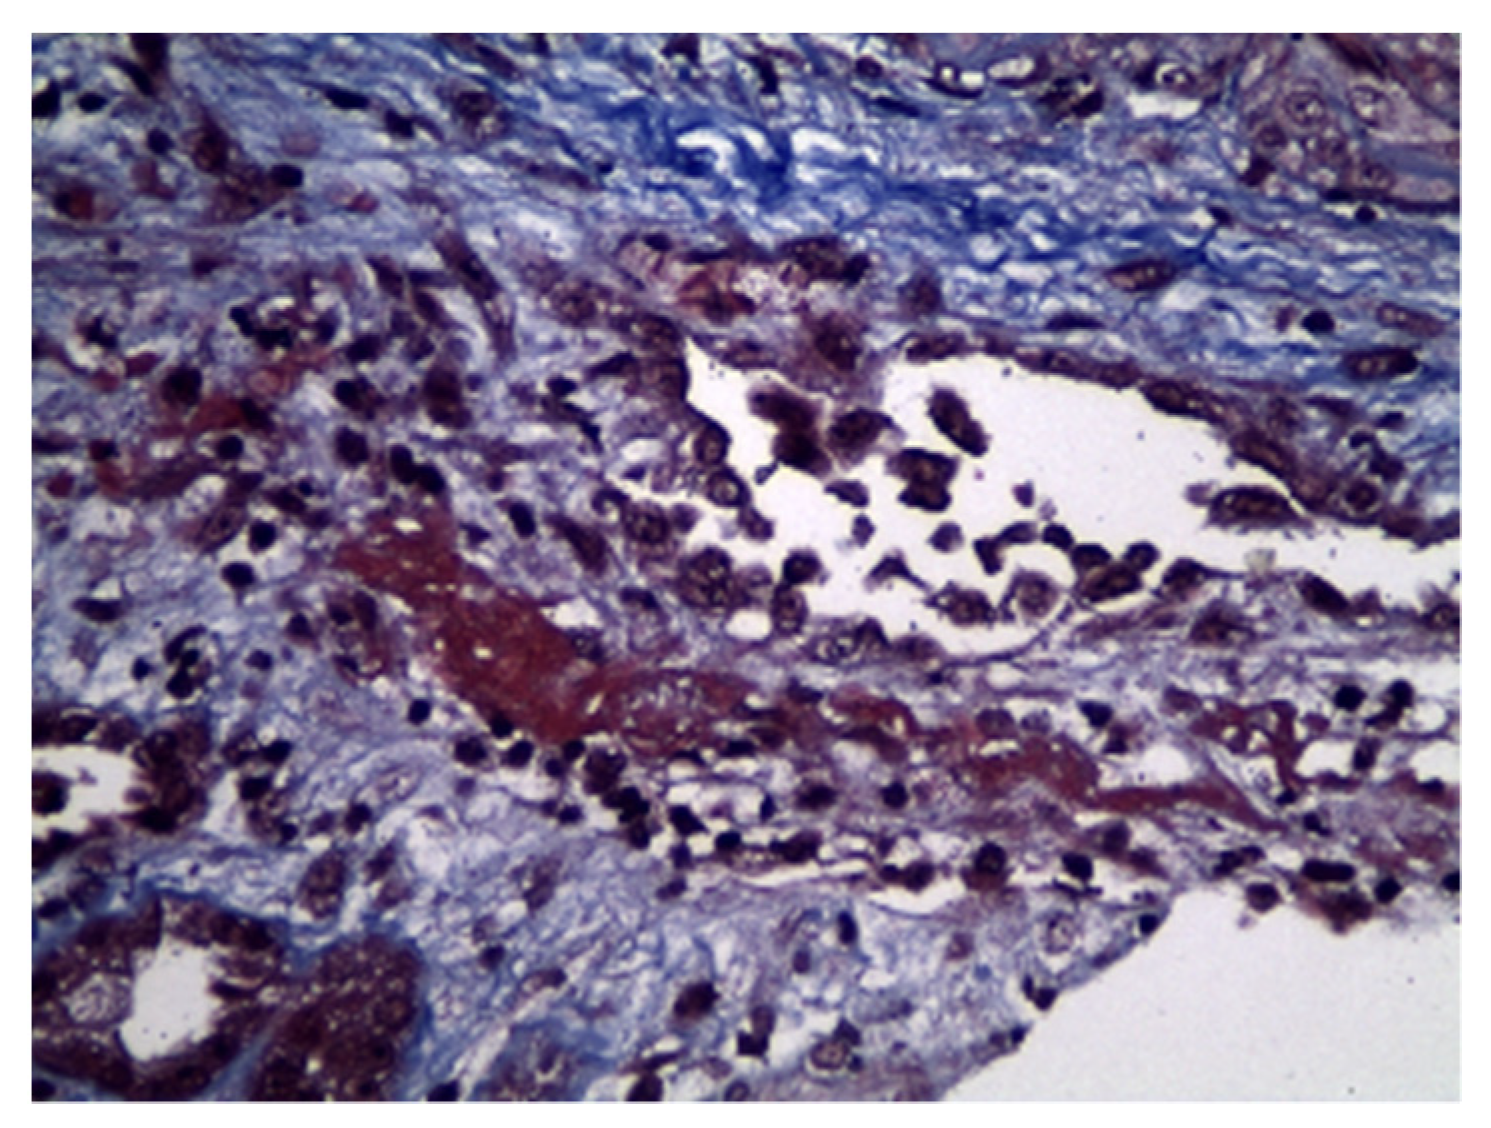

2. Case Description